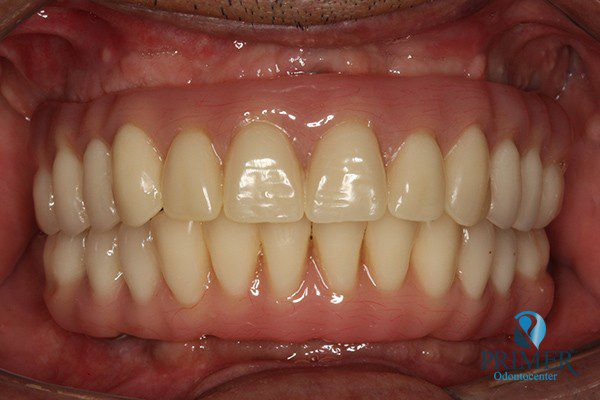

Realizado em: Agosto de 2012Detalhes do tratamento: Implantes instalados imediatamente após extrações de dentes inferiores e prótese fixa sobre implantes (instalada 72 horas após a cirurgia).

Fiz tratamento odontológico com Dr. Alexandre e Dra. Mariza. Foi muito bom, gostei muito e estou muito satisfeita. Com Dr. Alexandre fiz cirurgia e implante. Foi muito bom não sentir dor, foi perfeito. Com Dra. Mariza fiz prótese fixa sobre implante inferior e prótese total “normal” superior. Estou muito satisfeita com o trabalho deles!

- Depois

- Sorriso final